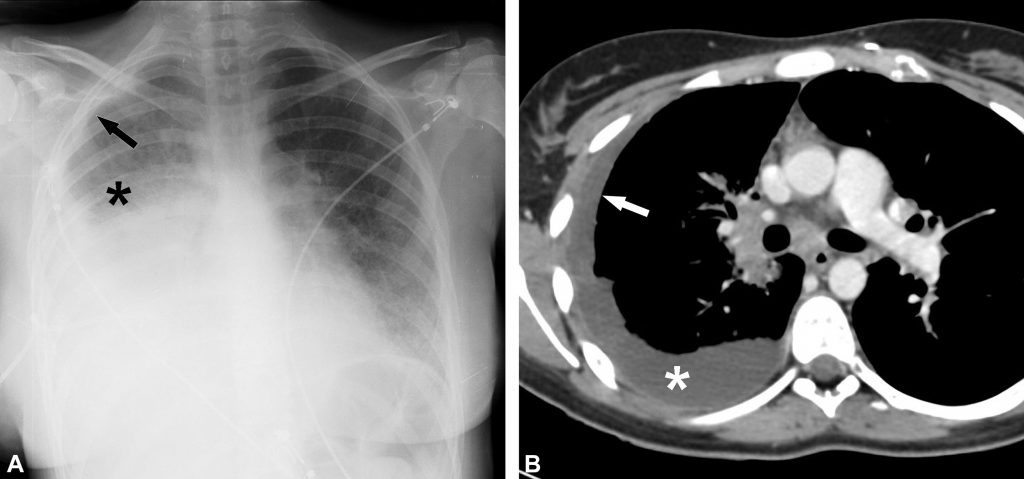

Fig. 91.5. Radiographie de face et scanner d’un épanchement pleural droit compressif.

L’hémithorax droit est entièrement opaque (astérisque en A) et la trachée est légèrement refoulée vers la gauche (flèches en A). Le scanner chez le même patient montre l’épanchement pleural droit de grande abondance (astérisque en B) refoulant le médiastin vers la gauche (flèches en B).

Source : CERF, CNEBMN, 2022.